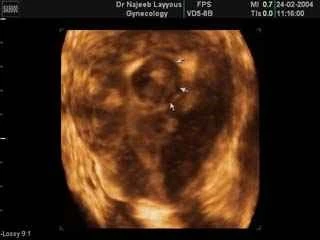

يمكن تشخيص الألياف الرحمية بواسطة الفحص السريري الذي يعتمد على شكوى المريضة من حيث الأعراض التي تعاني منها ، والفحص من قبل الطبيب، إلا إن هذا النوع من التشخيص لا يمكن الاعتماد عليه خوفاً من اختلاط التشخيص بأمراض أخرى تشارك الألياف الرحمية بنفس الأعراض مثل مرض البطانة الرحمية الهاجرة أو أكياس المبيض ولهذا السبب يجب أن يجرى فحص بواسطة جهاز الالتراساوند (الموجات فوق

الصوتية)، لكل مريضة تشكو من نزيف مهبلي أو آلام شديدة في البطن عند زيارتها الأولى للطبيب

الصوتية)، لكل مريضة تشكو من نزيف مهبلي أو آلام شديدة في البطن عند زيارتها الأولى للطبيبوفحص الالتراساوند المهبلي هو فحص سريع ويعطي معلومات دقيقة إلا أن ذلك يتطلب مهارة ومعرفة علمية بما هو طبيعي وما هو غير ذلك من قبل الطبيب المعالج، ومراقبة ذلك على جهاز الالتراساوند لإعطاء صورة أوضح ومعلومات أدق ولمنع أي التباس في التشخيص كما يمكن النظر في داخل الرحم بواسطة المنظار الرحمي

هناك حالات تتشابه في تشخيصها مع الألياف الرحمية وأهمها كما ذكرنا سابقاً مرض البطانة الرحمية الهاجرة حيث تتداخل بطانة الرحم مع جدار الرحم مما يؤدي إلى زيادة في سماكة جدار الرحم وتضخم في الرحم وهذا يمكن ملاحظته من خلال فحص الالتراساوند في حين ترى الألياف كمناطق دائرية لها حدود واضحة، فقبل الانتقال للمرحلة العلاجية يجب أن يكون التشخيص قائماً على أساس من الثقة حيث تتحكم في العلاج عوامل منها : حجم الليف وموقعه من الرحم ومدى حدة الأعراض التي يسببها